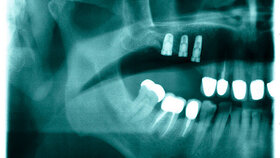

Nachdem die Implantate im August inseriert und die Stifte eingesetzt worden waren, sollte sich die Patientin erneut im Oktober vorstellen. Bei diesem Termin teilte ihr der Zahnarzt mit, dass noch bis Ende März mit der Endbehandlung gewartet werden müsste, da eine weitere Regeneration des Zahnfleischs notwendig sei.

Auch eine "überlange Behandlungszeit" konnte der Sachverständige nicht bestätigen. "Vielmehr sei bei einer Versorgung mit Implantaten eine gewisse Einheilzeit zu berücksichtigen", heißt es im Urteil. "Diese liegt nach Angaben des Sachverständigen im Bereich von drei bis sechs Monaten, so dass im Falle der Klägerin keine Verzögerung der Behandlung festzustellen sei."